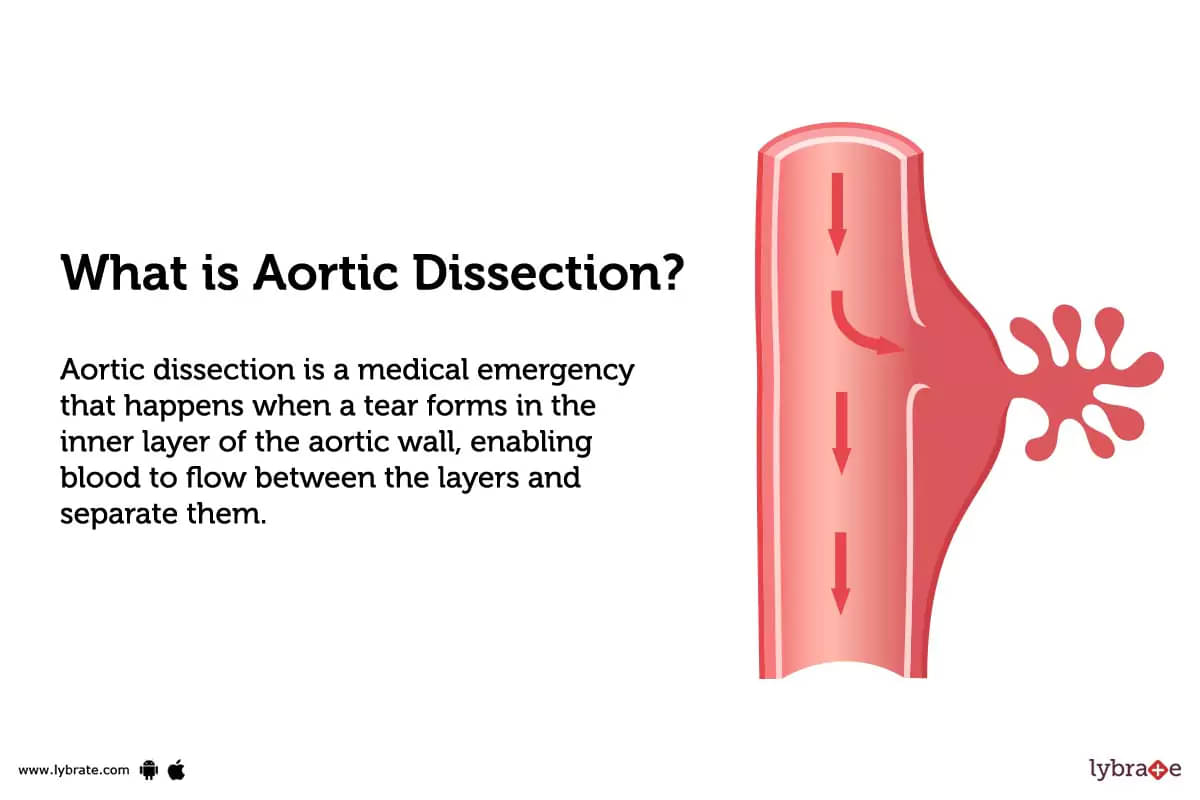

Aortic Dissection Without Chest Pain

Aortic Dissection Without Chest Pain

Aortic Dissection